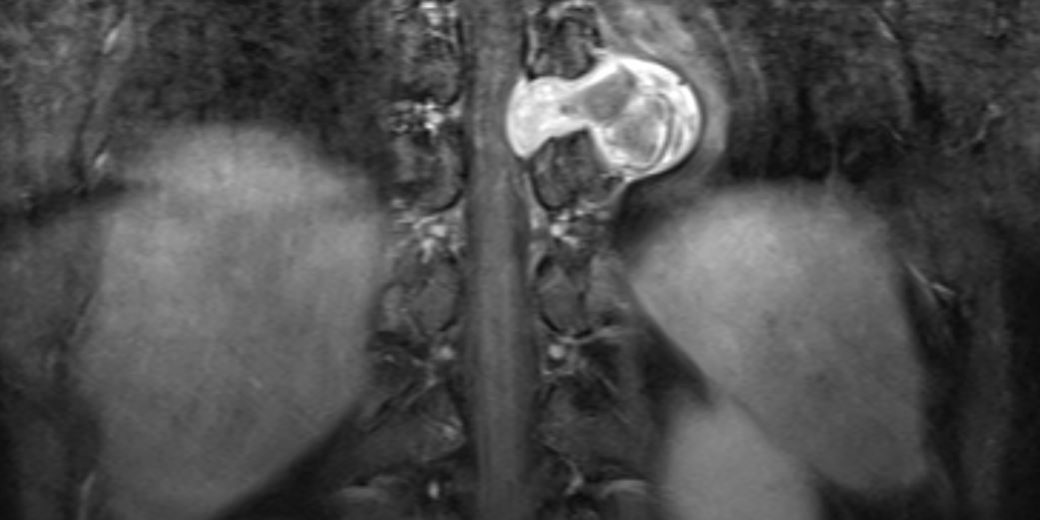

Θωρακικό Σβάννωμα Θ9/Θ10